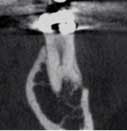

In our practice, we treat many patients who cannot tolerate root canal treatment. They require I.V. sedation. Having the capability of also doing a Promax 3D image with the same imaging machine allows for more proficient and expeditious treatment during sedation. Having prior radiographic knowledge of an additional canal and tooth anatomy makes for a shorter anesthesia time. It’s a safer and less expensive procedure for the patient.